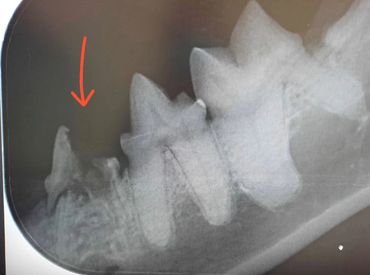

Syöpymä alkaa hammassementistä ja usein hampaan kaula-alueelta, aiheuttaa hampaan juurialueella normaalin rakenteen häviämisen. Edetessään sairaus aiheuttaa hampaan juuren sulautumisen leukaluuhun. Hampaan ydin säilyy elävänä kuitenkin hyvin pitkään. Vähitellen muutokset etenevät juurialueelta kruunun dentiiniin ja sitten hampaan kiilteeseen. Pikkuhiljaa kiille murtuu tai resorpoituu ja aiheuttaa siten kipua syöpymän puhjetessa suuontelon puolella. Vauriot tulevat tyypillisimmin alapremolareissa ja kulmahampaissa.

Hammassresorptioita on eri tyyppejä. Toisessa muodossa hammasjuuri sulautuu leukaluuhun (korvautuva, tyyppi 2) ja toisessa hampaaseen tulee tulehduskeskuksia (tulehduksellinen, tyyppi 1). Hampaassa voi esiintyä myös molempia tyyppejä (seka, tyyppi 3)

Ohessa röntgenkuva alakulmahampaasta, missä juurialueella jo pitkälle edennyt syöpymämuutos. Lisäksi havaitaan ensimmäisen premolarin kruunun irronneen syöpymämuutosten vuoksi.